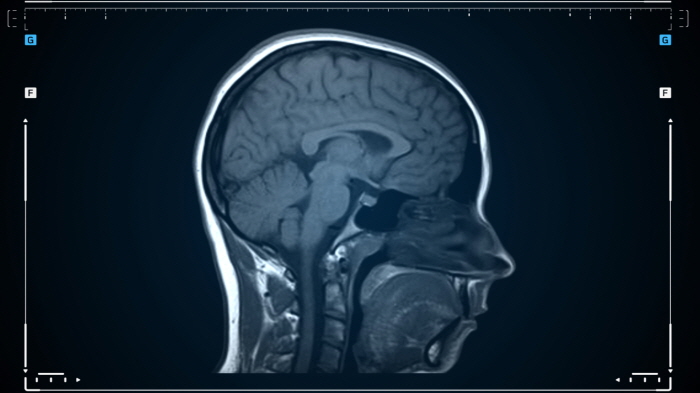

이 질환은 발작, 두통, 인지 기능 저하, 뇌수종 등 다양한 증상을 유발하며, 진단을 위해 MRI, CT 촬영 및 혈액 검사가 필요합니다.

ㆍ MRI(자기공명영상): 뇌 속 유충의 위치와 크기를 정확히 확인할 수 있습니다.

ㆍ CT(컴퓨터 단층촬영): 유충에 의해 뇌에 생긴 병변을 확인합니다.